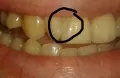

Заметила на эмали зуба какое-то пятнышко. Что это, прокомментируйте пожалуйста, какие действия предпринять? Фото прилагаю (отметила черным).

Комментарий №160945

• Это пятнышко ― кариес. Обратитесь к врачу, данную проблему можно решить в одно посещение.